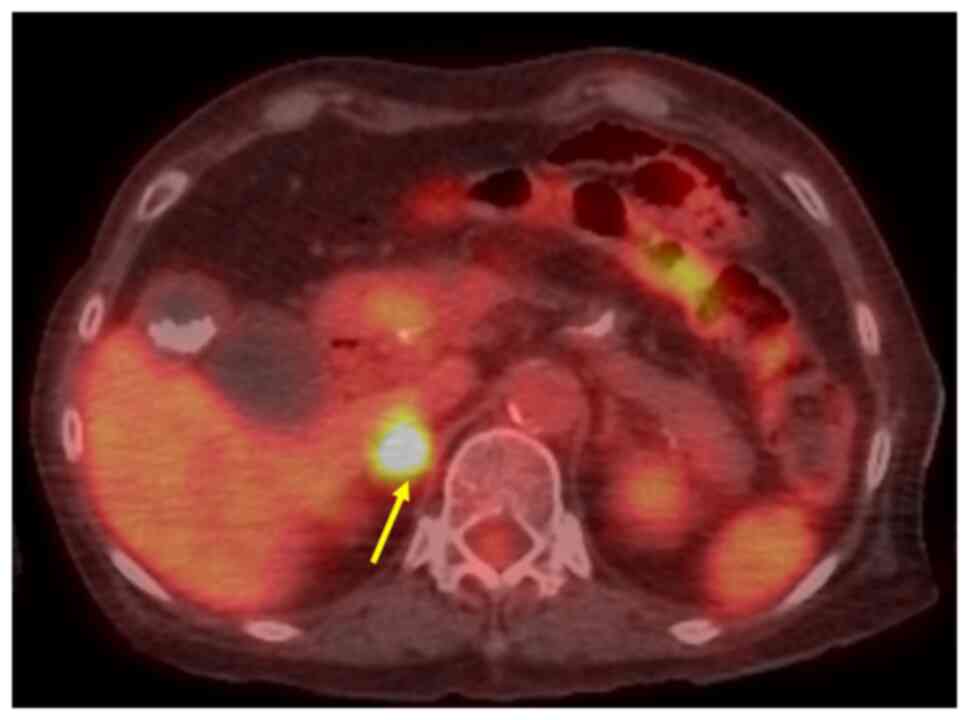

Methotrexate‑related other iatrogenic immunodeficiency‑associated lymphoproliferative disorder (MTX‑OIIA‑LPD) is prone to extranodal involvement but rarely involves the central nervous system (CNS). The present study reports a case of MTX‑OIIA‑LPD of the CNS discovered during medication‑related osteonecrosis of the jaw (MRONJ) treatment in a 76‑year‑old woman with rheumatoid arthritis (RA). The chief complaint of the patient was bone exposure and pain in the right mandibular molar. The patient had been receiving MTX for RA and alendronate sodium hydrate for osteoporosis, followed by denosumab. Treatment was initiated based on a diagnosis of MRONJ. However, the patient experienced lightheadedness and floating dizziness afterwards. Examinations revealed scattered neoplastic lesions in the brain. The histopathological diagnosis was diffuse large B‑cell lymphoma. A systemic search also revealed adrenal involvement. Since the patient was taking MTX, a diagnosis of MTX‑OIIA‑LPD was made and MTX was discontinued. Chemotherapeutic agents were administered since the central lesions became symptomatic. The MTX‑OIIA‑LPD lesions in the brain and adrenal glands completely resolved 8 months after onset. The physical condition of the patient improved, and the bone‑exposed areas became epithelialized. Reports on MTX‑LPD in the oral and maxillofacial region are few, which may delay its diagnosis. Therefore, biopsy of oral lesions in patients with MRONJ who are taking MTX and collaboration with related diagnostic departments, such as rheumatology and hematology, must be done to initiate the diagnosis and treatment of extraoral MTX‑LPD.